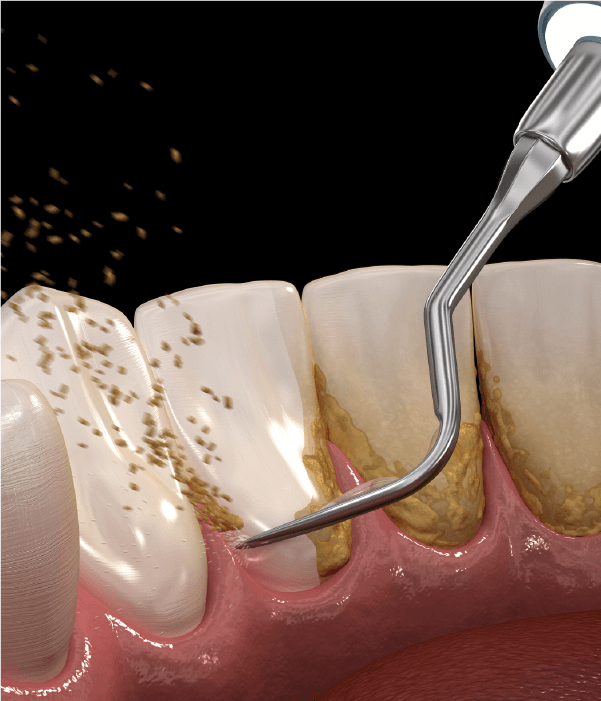

歯石がたまり、細菌が歯肉に繁殖し歯茎を悪化していく恐ろしい病気です。全身疾患と関連が深く、定期的な口腔ケアが必要です。当院では専門的な歯周病治療を行い、全身疾患から守ります。

歯・土台・歯周組織の口腔ケアメンテナンス

歯周組織の腫れや炎症を診断し、口腔内の常在細菌のバランスを保つことで、むし歯や歯周病になりにくい口腔環境になります。歯周組織を健康な状態に維持し、歯の疾患から守るように専門的な治療を行います。

口腔清掃:歯石を除去する

歯周病治療:歯周組織をキレイにする

PMTC:口腔内の健康を維持する